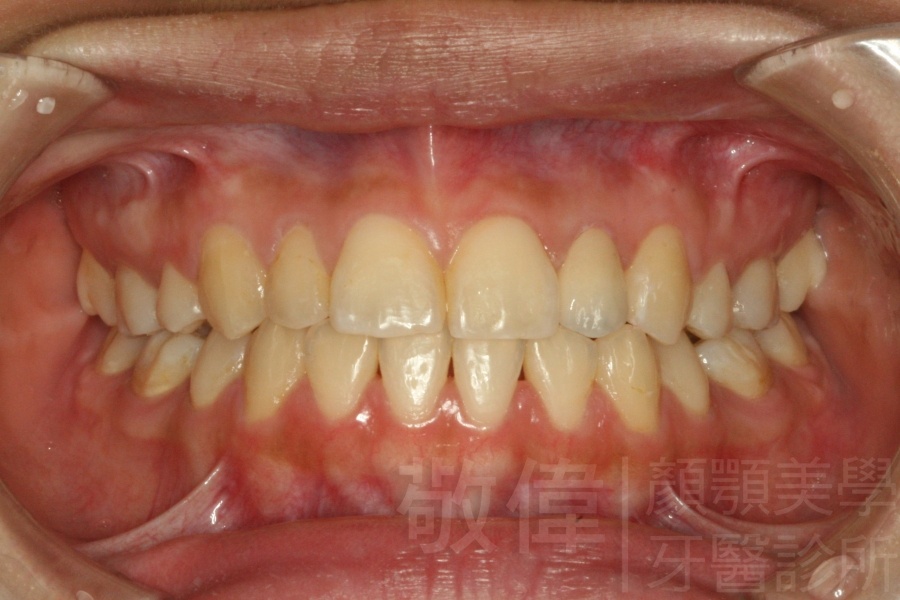

| 7 | 前牙美容 | 矯正+晶鑽全瓷冠 | ||